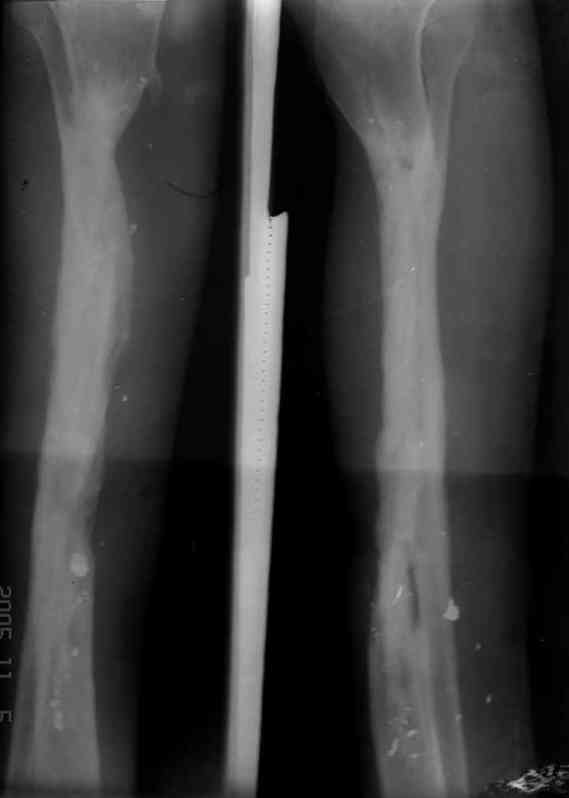

5. Ну и чтобы не быть голословным. Молодой человек подорвался на фугасе (Чечня, 2005 год). Свежие рентгенограммы:

Соответственно ожоги и дефект мягких тканей, переломы костей стопы и пр. Наложили аппарат

Илизарова (как придется), хирургически обработали и героически заживляли мягкие ткани с многочисленными кожными пластиками. В итоге через полгода я принял его вот таким: